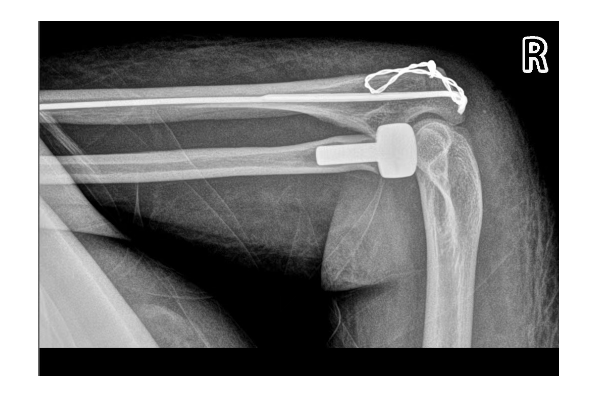

右侧桡骨头置换术+右侧尺骨鹰嘴骨折切开复位内固定术

顺利完成

配合快速康复

玉芝的肘关节功能逐渐恢复